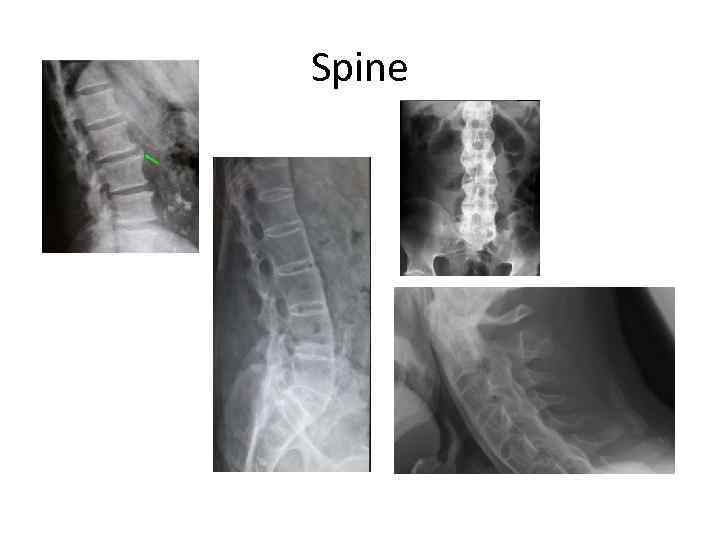

Spine